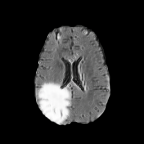

Brats MRI T1 Scans, FLAIR, Tumors. Lastly, we used a dataset of brain MRI scans [28] with two modalities: T1 (naive) and FLAIR (T2 Fluid Attenuated Inversion Recovery) [15]. We adapt the protocol that Cohen et al. [9] used for the Brats2013 datasets [27] to the more recent Brats2018 [3] dataset by varying the percentage of scans with tumors in the target domain. We selected transverse slices from the to range in the caudocranial direction [1] for both T1 and FLAIR scans. Each scan was classified as tumorous if more than of its pixels were labeled as such, and as healthy if it contained no tumor pixels. The training set contains images from each modality, with all source images (T1) being healthy and the target domain (FLAIR) comprising tumorous scans. The test set contains paired scans of healthy brains.

We label each scan as tumorous if more than of its pixels are labelled as such, and as healthy if it contains no tumor pixels. We only use high-grade gliomas (HGG) instead of low-grade gliomas (LGG) as the are more easily observable [24]. In total, we obtain 5035 pathological pairs and 1135 healthy pairs. The train set is composed of a source domain of T1 images of healthy brains, while the target domain set is composed of FLAIR scans of which (60%) are tumorous and healthy. The test set is composed of aligned scans of healthy brains in both modalities.